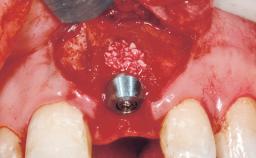

A 30-year-old female patient was referred to the office for the treatment of tooth 11. Her chief concern at the initial visit was to inquire, “Why is my tooth pink?” Upon clinical examination, it was determined that tooth 11 had a previous history of trauma and that the clinical crown had become noticeably pink in color as a result of internal resorption. This diagnosis was confirmed radiographically, indicating a large radiolucency involving the central and distal portions of the clinical crown. It was determined that restoration of this tooth was not possible, and that extraction was indicated. The presence of a mid-line diastema, which the patient wanted to reproduce, directed the treatment plan for tooth replacement utilizing a dental implant.

Bone Augmentation Horizontal|Simultaneous

Augmentation Materials Autogenous chips|Membrane

Socket Integrity Sufficient, with intact bone walls

Bone Volume Sufficient, with intact walls